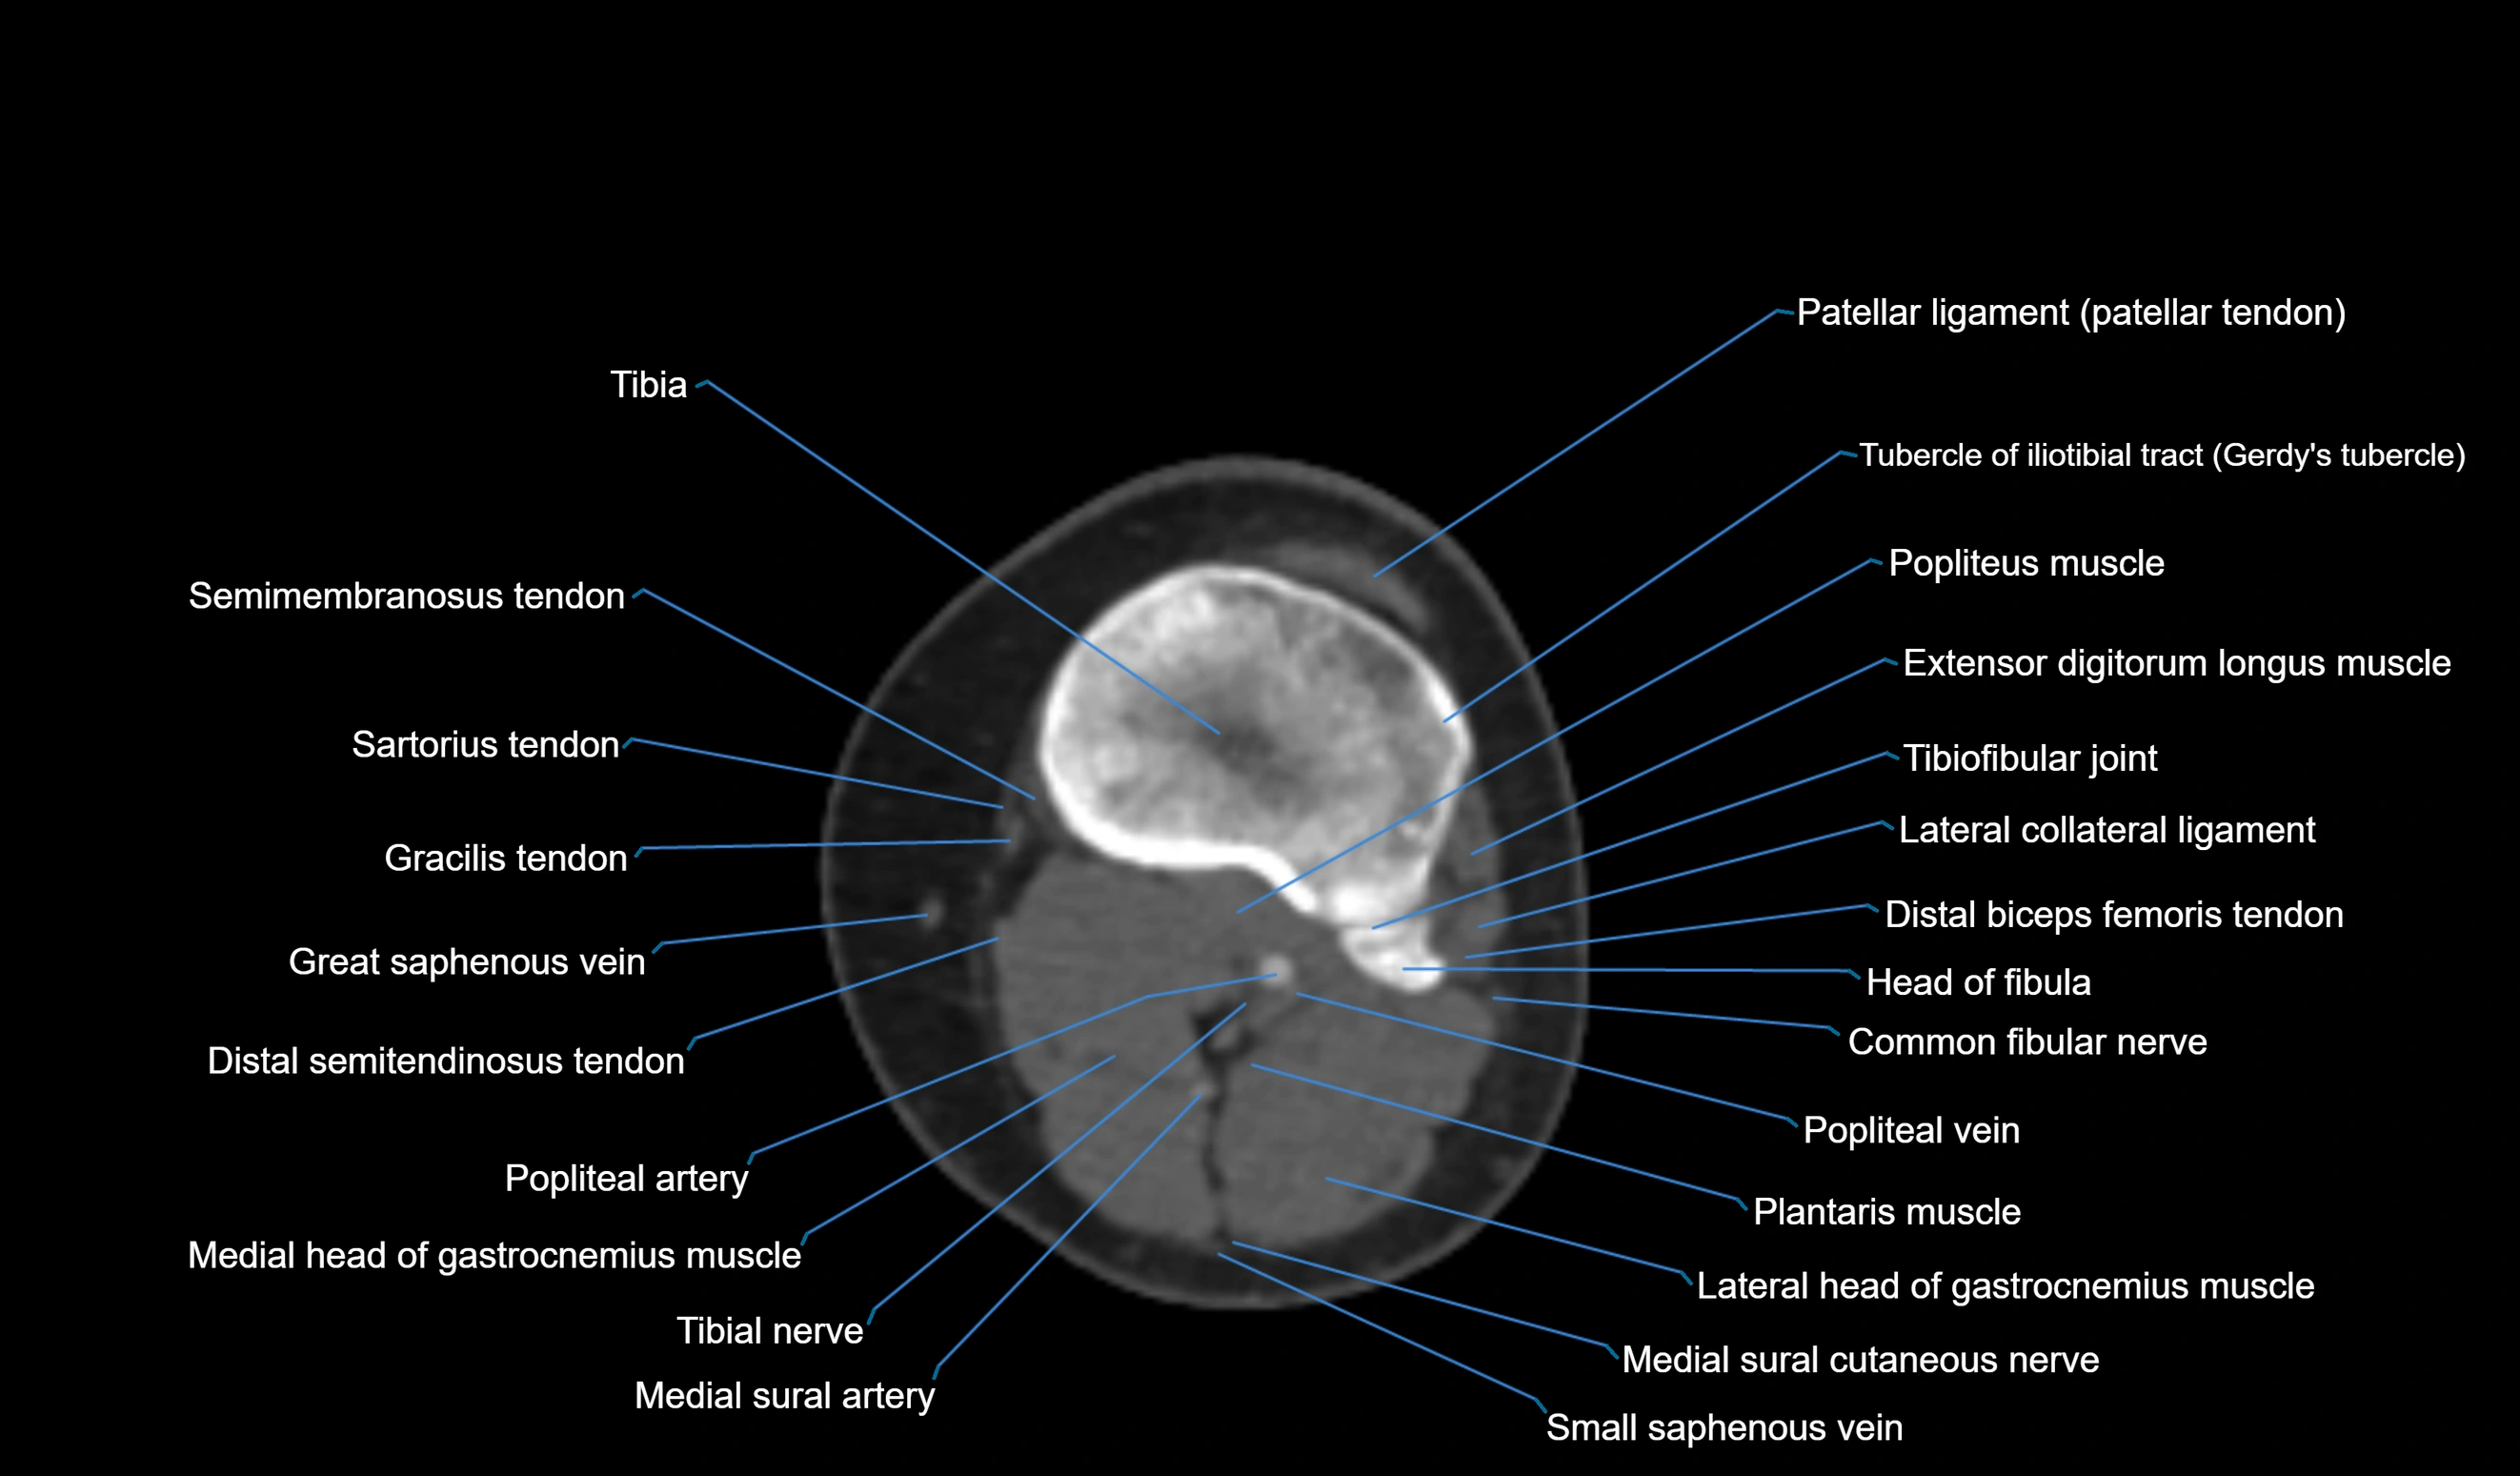

- Body of tibia

- Extensor digitorum longus muscle

- Fibula

- Gerdy’s tubercle

- Gracilis tendon (Distal)

- Head of fibula

- Lateral collateral ligament

- Lateral head of gastrocnemius muscle

- Medial head of gastrocnemius muscle

- Patellar tendon (patellar ligament)

- Plantaris muscle

- Popliteal artery

- Popliteal vein

- Sartorius tendon (Distal)

- Small saphenous vein

- Superior tibiofibular joint

- Tibial nerve

- Tubercle of iliotibial tract